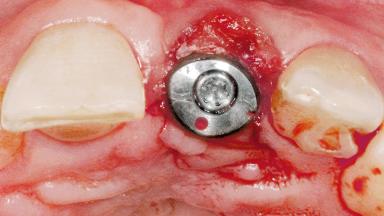

Late Flapless Placement of an Implant in a Maxillary Left Central Incisor Site

A 39-year-old male patient presented with a chief complaint of discomfort and gingival discoloration around his maxillary left central incisor. He was in good general health and was a non-smoker. His past dental history was significant because of the traumatic fracture of tooth 21 in a sporting accident at age 13. Initial dental treatment included endodontic therapy and a full-coverage restoration. The patient became symptomatic 5 years later, when structural failure of the tooth resulted in the dislodgment of the crown. Endodontic retreatment, apical surgery, and post-and-core restoration were performed.